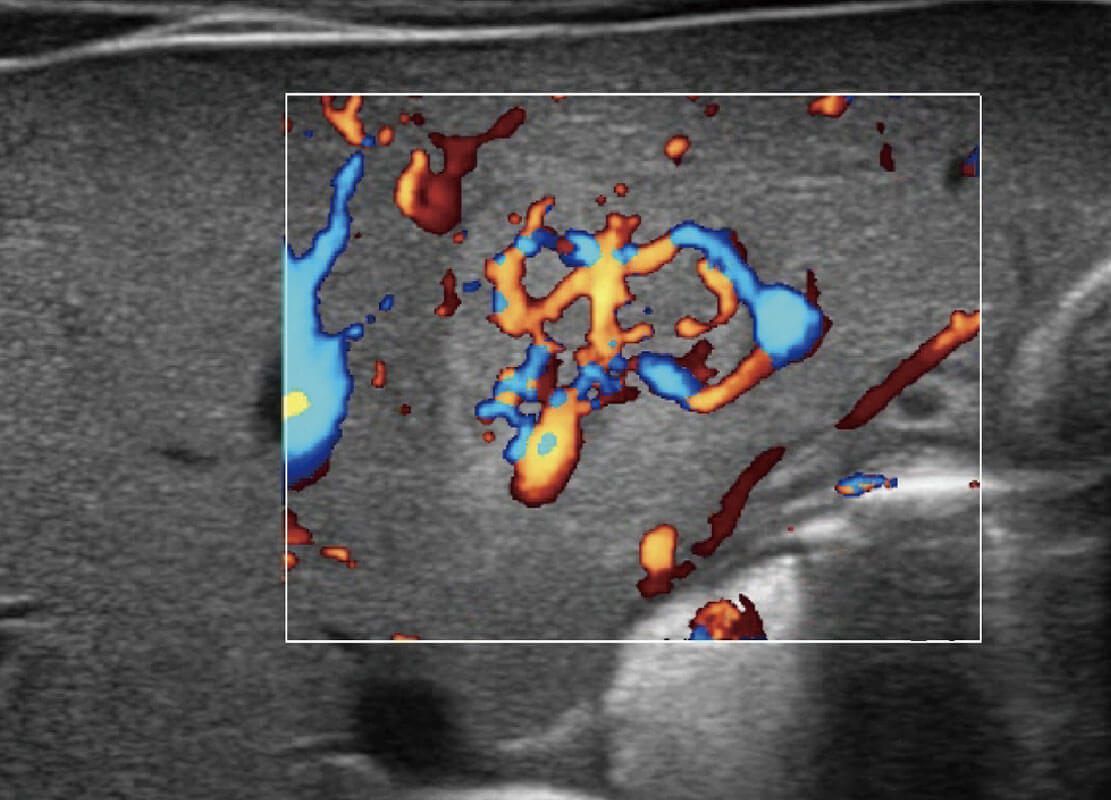

四腔心血流